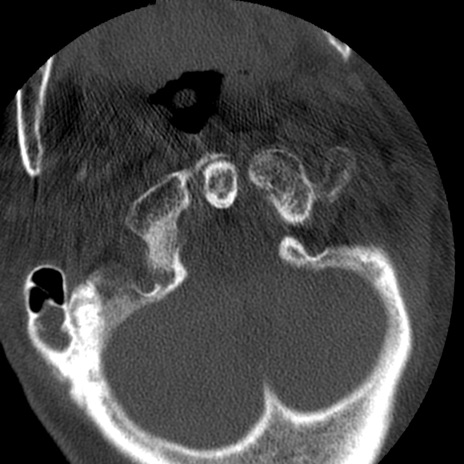

症例50 頚椎CT(横断像)

矢状断像